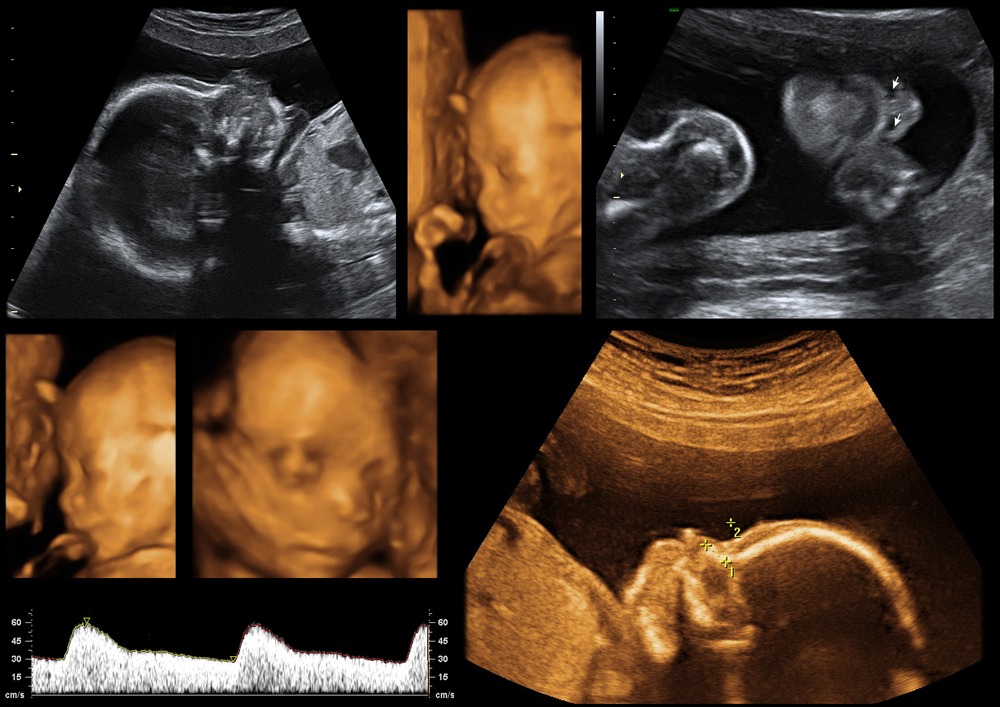

lifelinepanvel.com4D Fetal Ultrasound - RadRounds Radiology Network

lifelinepanvel.com4D Fetal Ultrasound - RadRounds Radiology Network

radrounds.comultrasound fetal radrounds embarazo prenatal

radrounds.comultrasound fetal radrounds embarazo prenatal

Pin On Motherhood Hospital

in.pinterest.com3D 4D Pregnancy Sonography - Dr. Panchal Lab & Diagnostics Centre

in.pinterest.com3D 4D Pregnancy Sonography - Dr. Panchal Lab & Diagnostics Centre

drpanchallab.comsonography ultrasound scans fetal

drpanchallab.comsonography ultrasound scans fetal